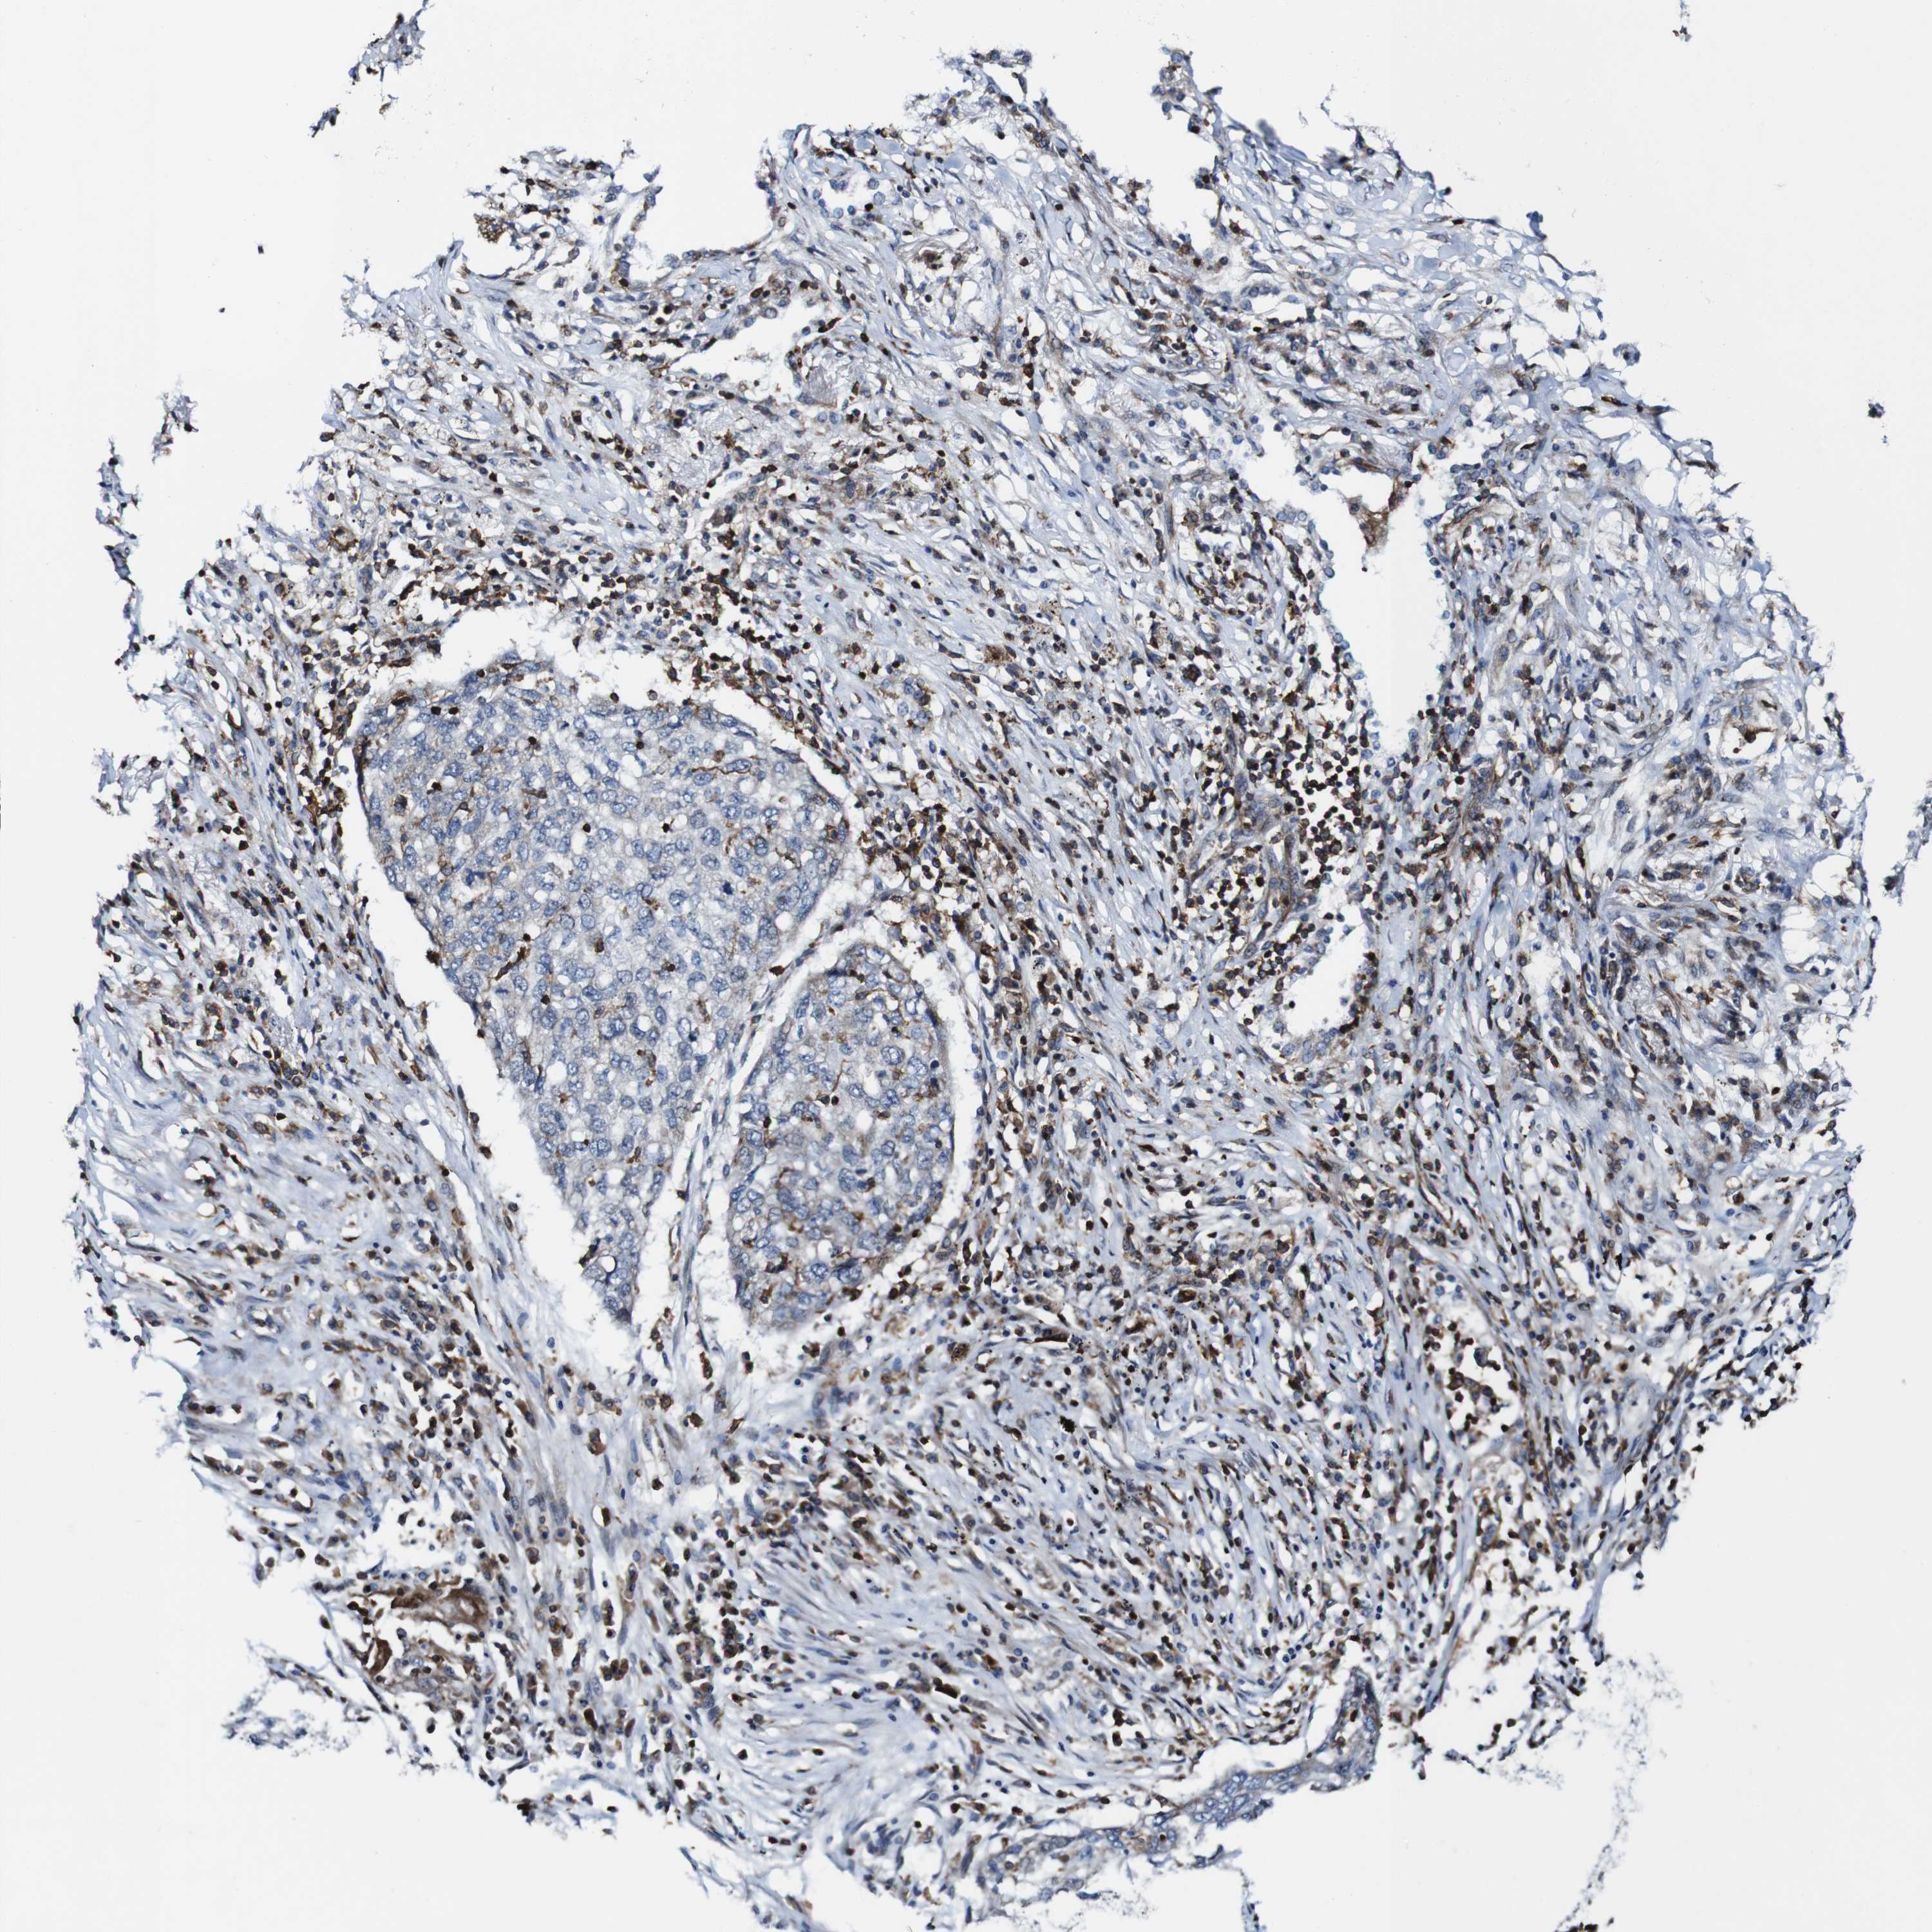

LUNG SQUAMOUS CELL CARCINOMA (TCGA) - Interactive survival scatter ploti

The Survival Scatter plot shows the clinical status (i.e. dead or alive) for all individuals in the patient cohort, based on the same data that underlies the corresponding Kaplan-Meier plots. Patients that are alive at last time for follow-up are shown in blue and patients who have died during the study are shown in red.

The x-axis shows the expression levels (FPKM) of the investigated gene in the tumor tissue at the time of diagnosis. The y-axis shows the follow-up time after diagnosis (years). Both axes are complimented with kernel density curves demonstrating the data density over the axes. The top density plot shows the expression levels (FPKM) distribution among dead (red) and alive patients (blue). The right density plot shows the data density of the survived years of dead patients with high and low expression levels respectively, stratified using the cutoff indicated by the vertical dashed line through the Survival Scatter plot. This cutoff is automatically defined based on the FPKM cutoff that minimizes the p-score. The cutoff can be changed by dragging the vertical line or by entering a cutoff value in the square labeled "Current cut-off".

Under the Survival Scatter plot the p-score landscape (black curve; left axis) is shown together with dead median separation (red curve; right axis). Dead median separation is the difference in median mRNA expression between patients who have died with high and low expression, respectively. It is calculated as follows: median FPKM expression of dead patients with high expression - median FPKM expression of dead patients with low expression. This is intended to aid the user in visually exploring custom cutoffs and the associated p-scores and dead median separation.

Individual patient data is displayed and can be filtered by clicking on one or more of the category buttons on the top of the page. Categories describing expression level and patient information include: high, low, alive, dead, female, male and tumor stages. The scale of the x-axis can be toggled between linear and log-scale by clicking on the "x log" button. Mouse-over function shows TCGA ID, patient information and mRNA expression (FPKM) for each patient.

& Survival analysisi

Kaplan-Meier plots summarize results from analysis of correlation between mRNA expression level and patient survival. Patients were divided based on level of expression into one of the two groups "low" (under cut off) or "high" (over cut off). X-axis shows time for survival (years) and y-axis shows the probability of survival, where 1.0 corresponds to 100 percent.

JAK2 is not prognostic in Lung Squamous Cell Carcinoma (TCGA)

: 5.28